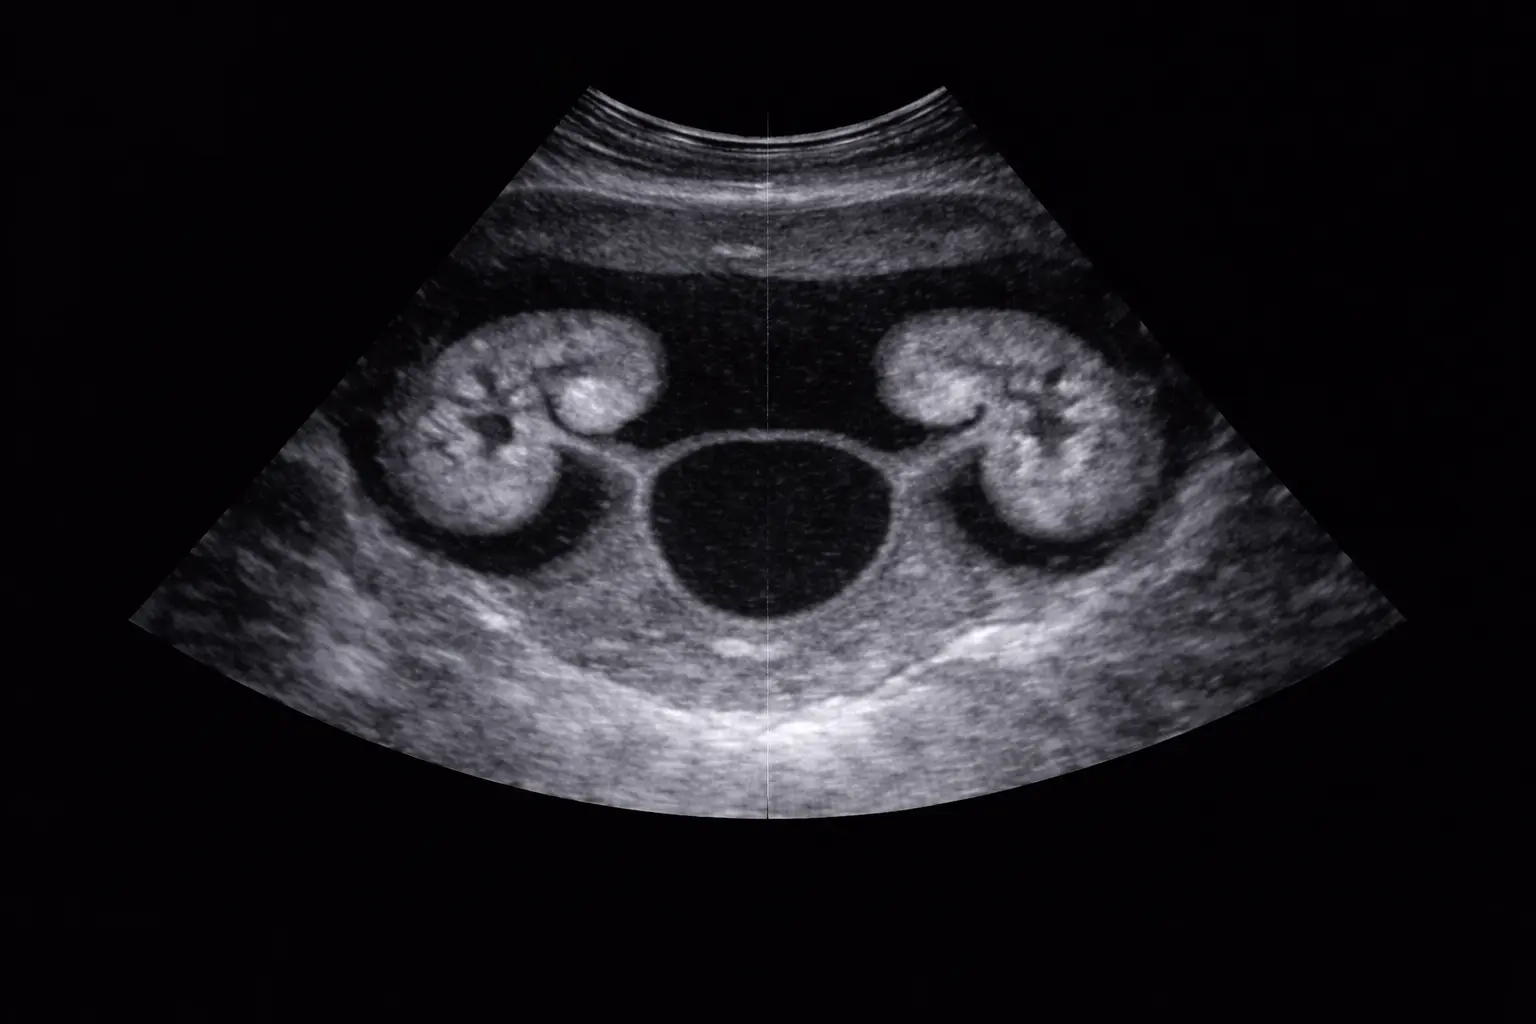

Kidneys & bladder scans

A specialized ultrasound to assess the urinary system. It is effective for detecting kidney stones, cysts, or obstructions and evaluating bladder health and emptying functions.